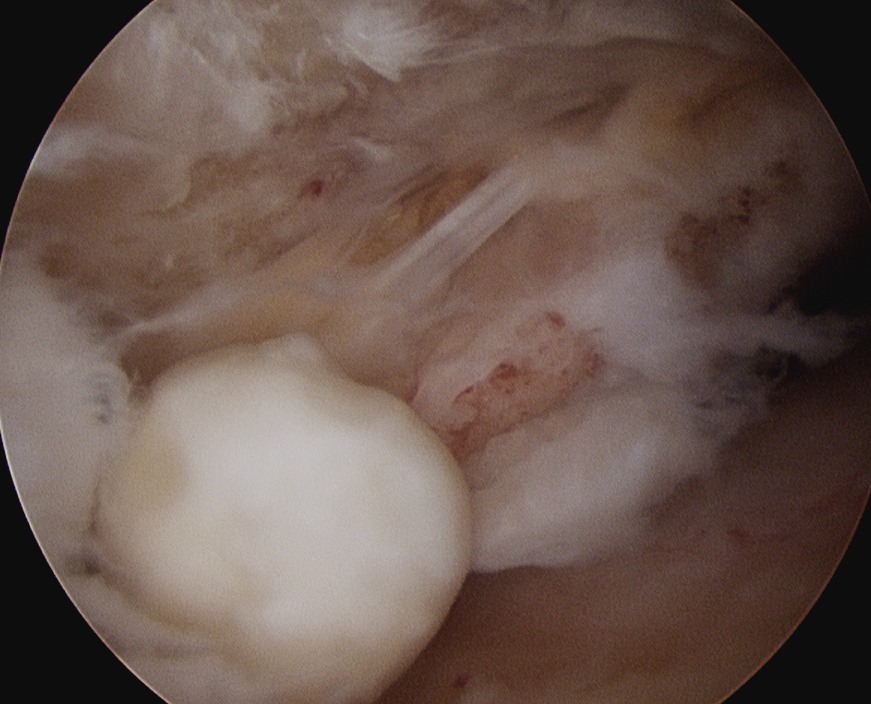

| Inferior glenohumeral ligament (IGHL) | |

Origin: Inferior 2/3 glenoid and labrum Insertion: Anatomical neck humerus

Anterior band: antero-inferior glenoid to 3 o'clock Posterior band: postero-inferior glenoid to 9 o'clock Axillary pouch between two bands |

| Most important ligament in terms of stability | Stabilizes arm at 90 degrees of abduction |

Anterior IGHL glenoid attachment |

IGHL humeral attachment |

Inferior recess

Loose body in inferior recess